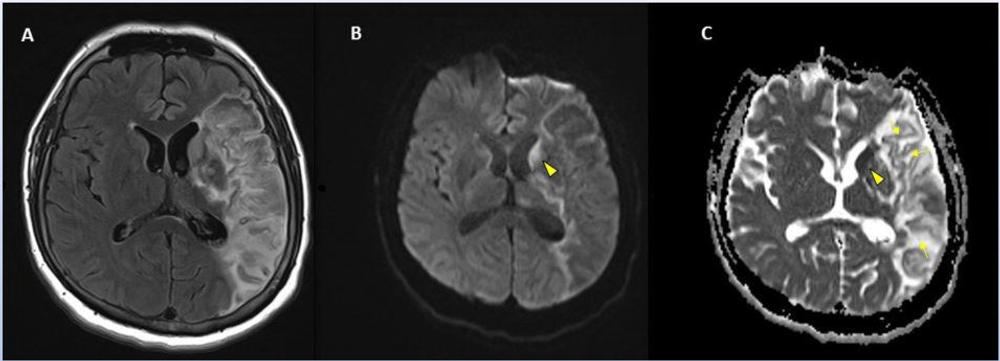

Figure 4. 62-year-old male with a past medical history of hypertension presenting with seizures.

Figure 5. 56-year-old male patient with diabetes and hypertension who presented with complaints of confusion.